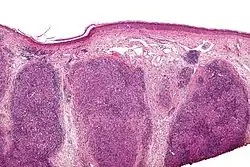

| Low magnification micrograph of a lymphoepithelioma-like carcinoma showing the characteristic squamoid nests in association with clusters of lymphocytes. H&E stain. | |